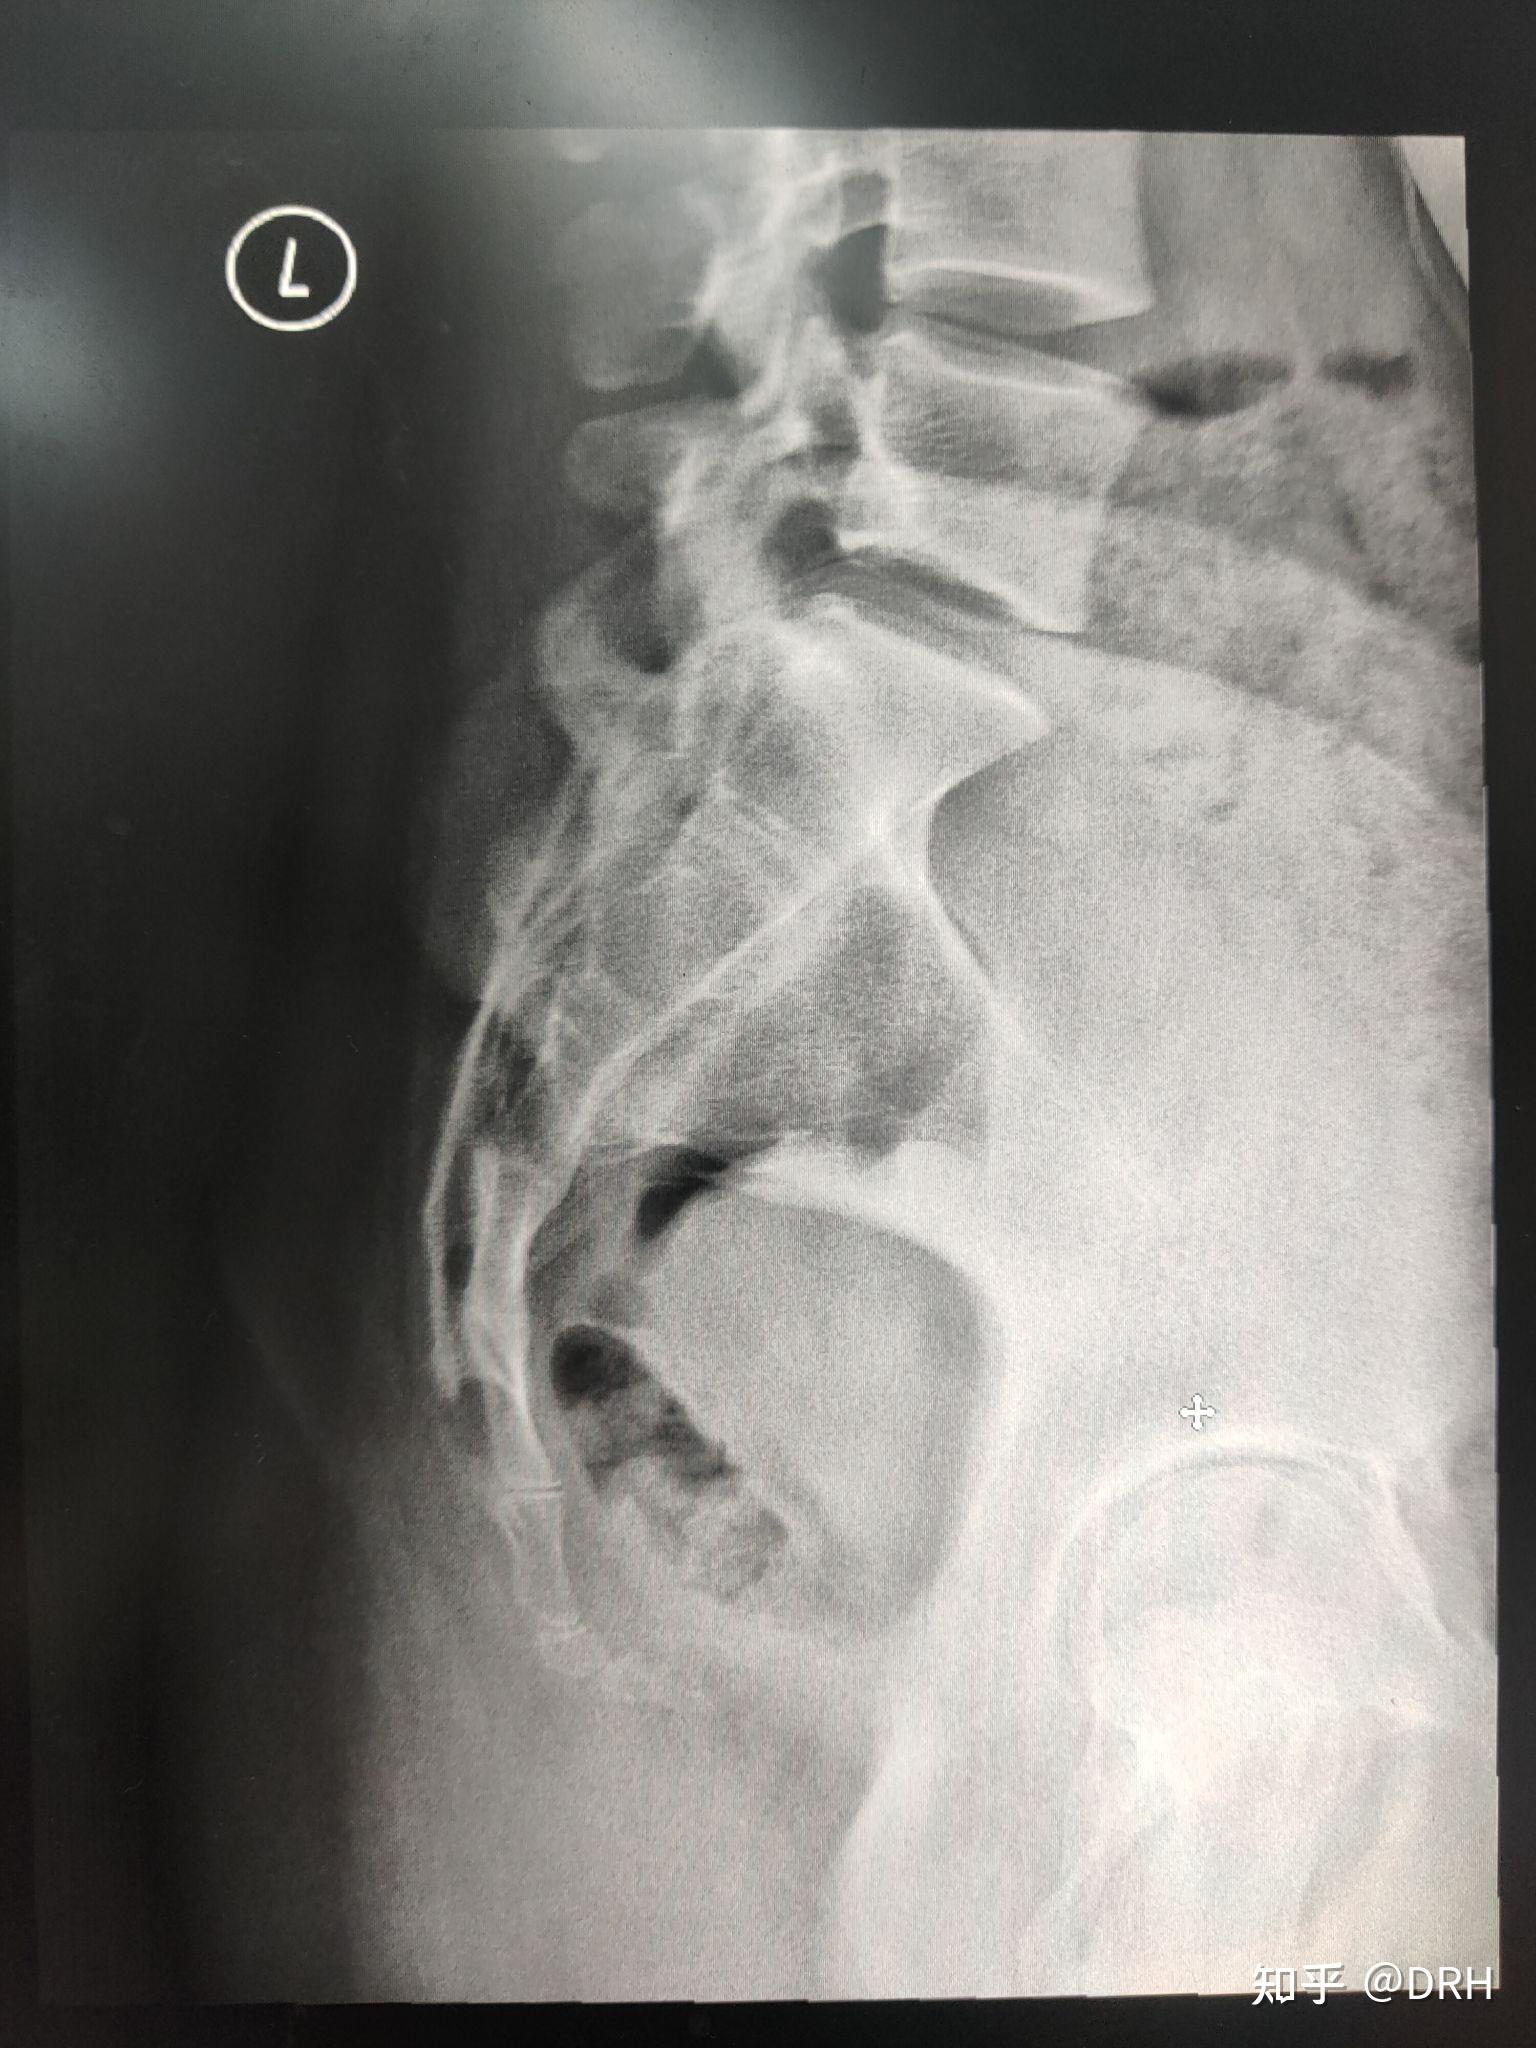

骶尾椎影像报告怎么写

拍摄骶尾椎正位片时,为啥要向足侧打10°-15°角?

基础巩固骶尾骨正侧位x线摄影

胸椎 腰椎 骶尾椎 影响解剖